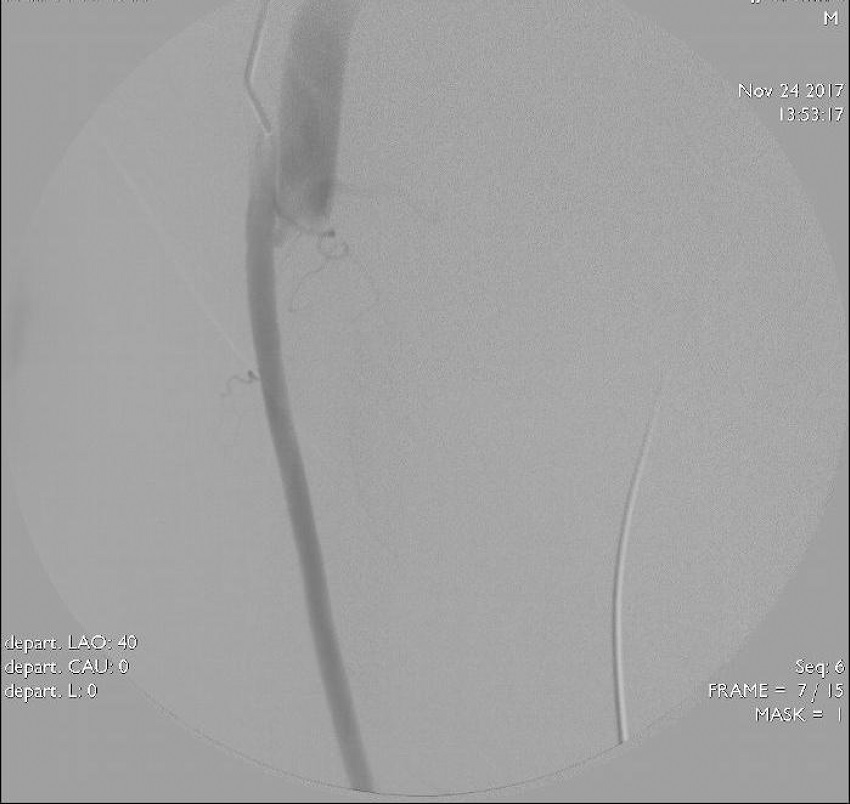

After consultation of interventional radiology, endovascular treatment was decided. Under local anesthesia, the right femoral artery was reached, and the right lower extremity angiograms were obtained after appropriate manipulations. A fistula was located between the superficial femoral arter and the superficial femoral vein (Figure 2). The femoral vein was reached after passing through the fistula tract. The catheter was then withdrawn slowly to try to embolize with cyanoacrylate (glue). However, the glue could not be stabilized due to the high flow. Although the balloon catheter was inflated for a long period with low pressure in the fistula region, the flow to the vein via fistula could not be prevented. Then, the patient was informed about the endovascular stent. However, the patient preferred a surgical intervention instead of stenting.